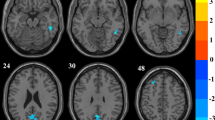

As mentioned above, the SA subtest is the only subtest that displayed a negative correlation with the total CAPS_IV scores. The application of simple MKL allowed quantitative association of SA scores by whole-brain resting-state mALFF in statistically significant accuracy (correlation = 0.28, P-value = 0.026; mean squared error = 8.36, P-value = 0.035) (corrected for multiple comparisons using the permutation test, both P < 0.05 was the significant level) (Fig. 1) in trauma survivors. The association was based on functional alterations across the whole brain, particularly in the left frontal middle gyrus and left precuneus, in addition to parietal lobes and occipital regions (Table 3, Fig. 2, and Additional file 1: Part 8). Table 3 expresses the neuroanatomical regions with a contribution to the association frame above 2% across all regions for the rs-fMRI-based MKL used to accurately predict SA. However, the simple MKL to the whole-brain resting-state mALFF data failed to make a statistically significant accurate quantitative association of SA scores (correlation = − 0.04, P-value = 0.497; mean squared error = 9.25, P-value = 0.712) (corrected for multiple comparisons using a permutation test, both P < 0.05 was the significant level) in PTSD patients (CAPS_IV score ≥ 40).

Multivariate map showing the weight of each part of brain region indicating its relative contribution to the regression function in the context of all other brain regions (color bar in arbitrary units). [a] left frontal middle gyrus; [b] left precuneus;[c] left superior parietal gyrus;[d] right precuneus